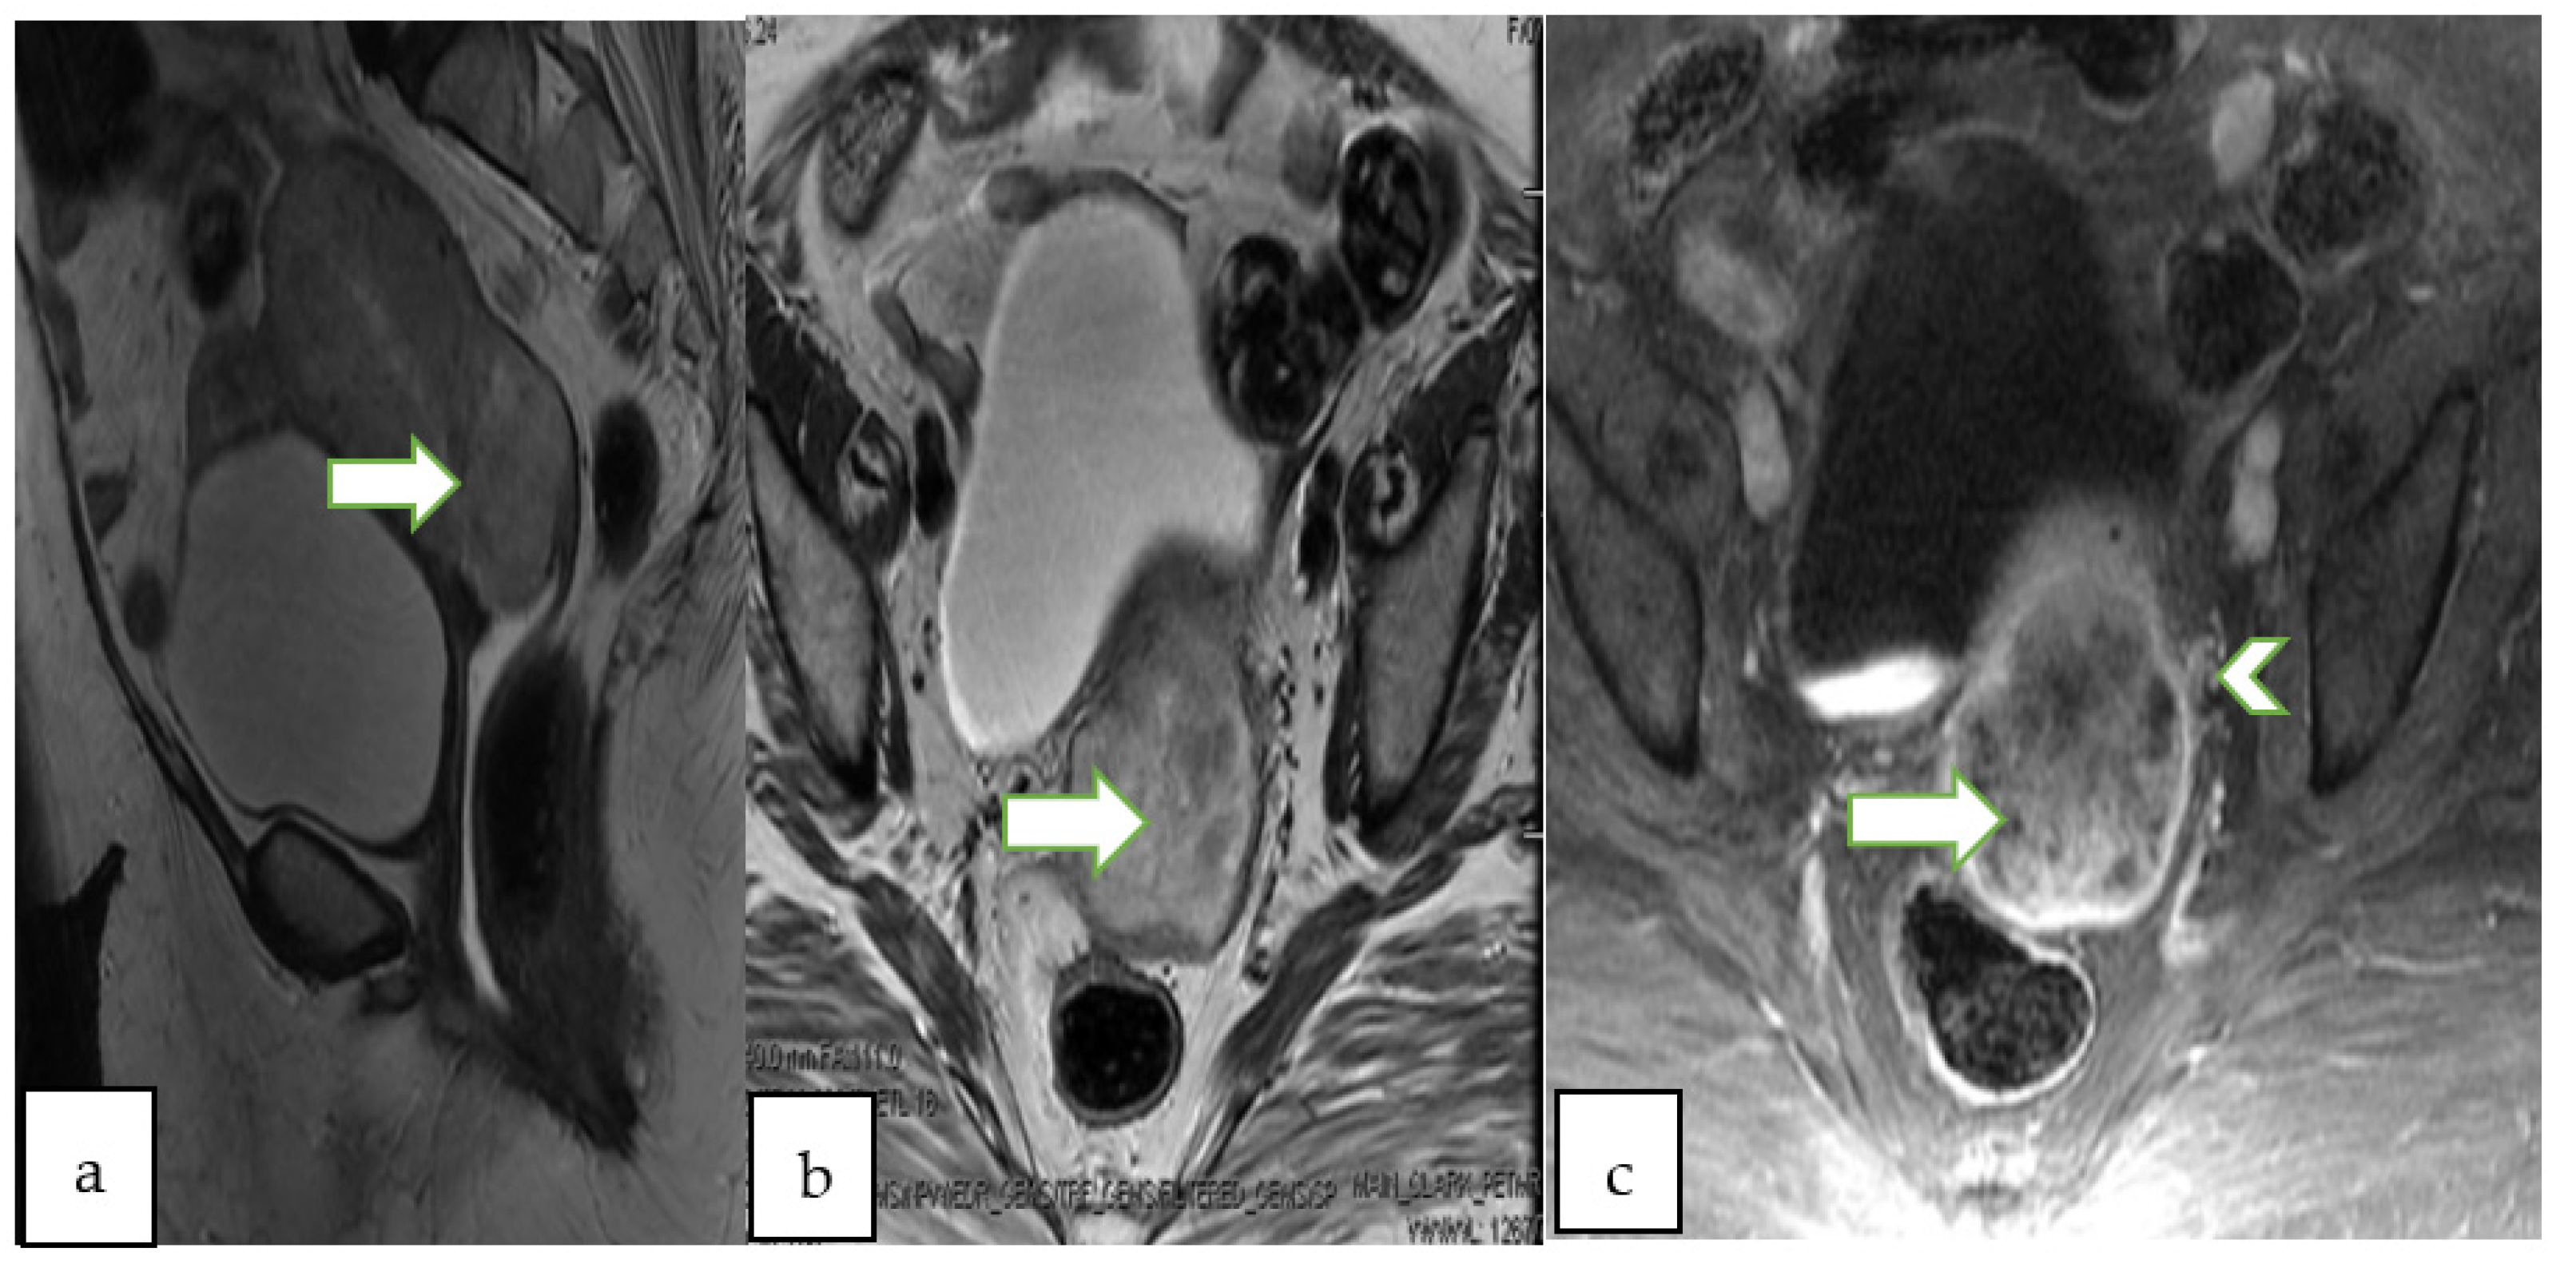

4.2. Magnetic Resonance Imaging (MRI)

- Thomassin-Naggara, I.; Poncelet, E.; Jalaguier-Coudray, A.; Guerra, A.; Fournier, L.S.; Stojanovic, S.; Millet, I.; Bharwani, N.; Juhan, V.; Cunha, T.M.; et al. Ovarian-Adnexal Reporting Data System Magnetic Resonance Imaging (O-RADS MRI) Score for Risk Stratification of Sonographically Indeterminate Adnexal Masses. JAMA Netw. Open 2020, 3, e1919896. [Google Scholar] [CrossRef]

- Sadowski, E.A.; Thomassin-Naggara, I.; Rockall, A.; Maturen, K.E.; Forstner, R.; Jha, P.; Nougaret, S.; Siegelman, E.S.; Reinhold, C. O-RADS MRI Risk Stratification System: Guide for Assessing Adnexal Lesions from the ACR O-RADS Committee. Radiology 2022, 303, 204371. [Google Scholar] [CrossRef]

| O-RADS MRI Score | Risk Category | Positive Predictive Value for Malignancy | Lexicon Description |

| 2 | Almost certainly benign | <0.5% | Cyst: Unilocular- any type of fluid content - No wall enhancement - No enhancing solid tissue * |

| Cyst: Unilocular–simple or endometriotic fluid content -Smooth enhancing wall -No enhancing solid tissue | |||

| Lesion with lipid content ** - No enhancing solid tissue | |||

| Lesion with solid tissue showing dark signal on T2/DWI -Homogeneously hypointense on T2 and DWI | |||

| Dilated fallopian tube-simple fluid content - Thin, smooth wall/endosalpingeal folds with enhancement - No enhancing solid tissue | |||

| Para-ovarian cyst–any type of fluid - Thin, smooth wall +/− enhancement - No enhancing solid tissue | |||

| 3 | Low risk | ~5% | Cyst: Unilocular–proteinaceous, hemorrhagic or mucinous fluid content - Smooth enhancing wall - No enhancing solid tissue |

| Cyst: Multilocular-Any type of fluid, no lipid content - Smooth septae and wall with enhancement-No enhancing solid tissue | |||

| Lesion with solid tissue (excluding T2 dark/DWI dark) - Low risk time intensity curve on DCE MRI | |||

| Dilated fallopian tube - Non-simple fluid: Thin wall/folds - Simple fluid: Thick, smooth wall/folds - No enhancing solid tissue | |||

| 4 | Intermediate risk | ~50% | Lesion with solid tissue (excluding T2 dark/DWI dark) - Intermediate risk time intensity curve on DCE MRI - If DCE MRI is not feasible, score 4 is any lesion with solid tissue (excluding T2 dark/DWI dark) that is enhancing ≤ myometrium at 30–40 s on non-DCE MRI |

| Lesion with lipid content - Large volume enhancing solid tissue | |||

| 5 | High risk | ~90% | Lesion with solid tissue (excluding T2 dark/DWI dark) - High risk time intensity curve on DCE MRI - If DCE MRI is not feasible, score 5 is any lesion with solid tissue (excluding T2 dark/DWI dark) that is enhancing > myometrium at 30–40 s on non-DCE MRI |

| Peritoneal, mesenteric or omental nodularity or irregular thickening with or without ascites |